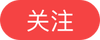

CT显示回盲部梗阻

两个月前,张阿姨突然出现腹痛、腹胀症状,当地医院检查后认为是阑尾炎,便开始抗感染治疗,可折腾了两个月,张阿姨的症状不仅没有缓解,反而越来越严重,最后连排气排便都没办法。家人立即带着张阿姨转至西安高新医院。CT检查后,结果却出乎意料,张阿姨并非阑尾炎,而是回盲部肿瘤引发的肠梗阻,而且肿瘤侵犯到右侧卵巢、腰大肌,并且出现多发肝转移。